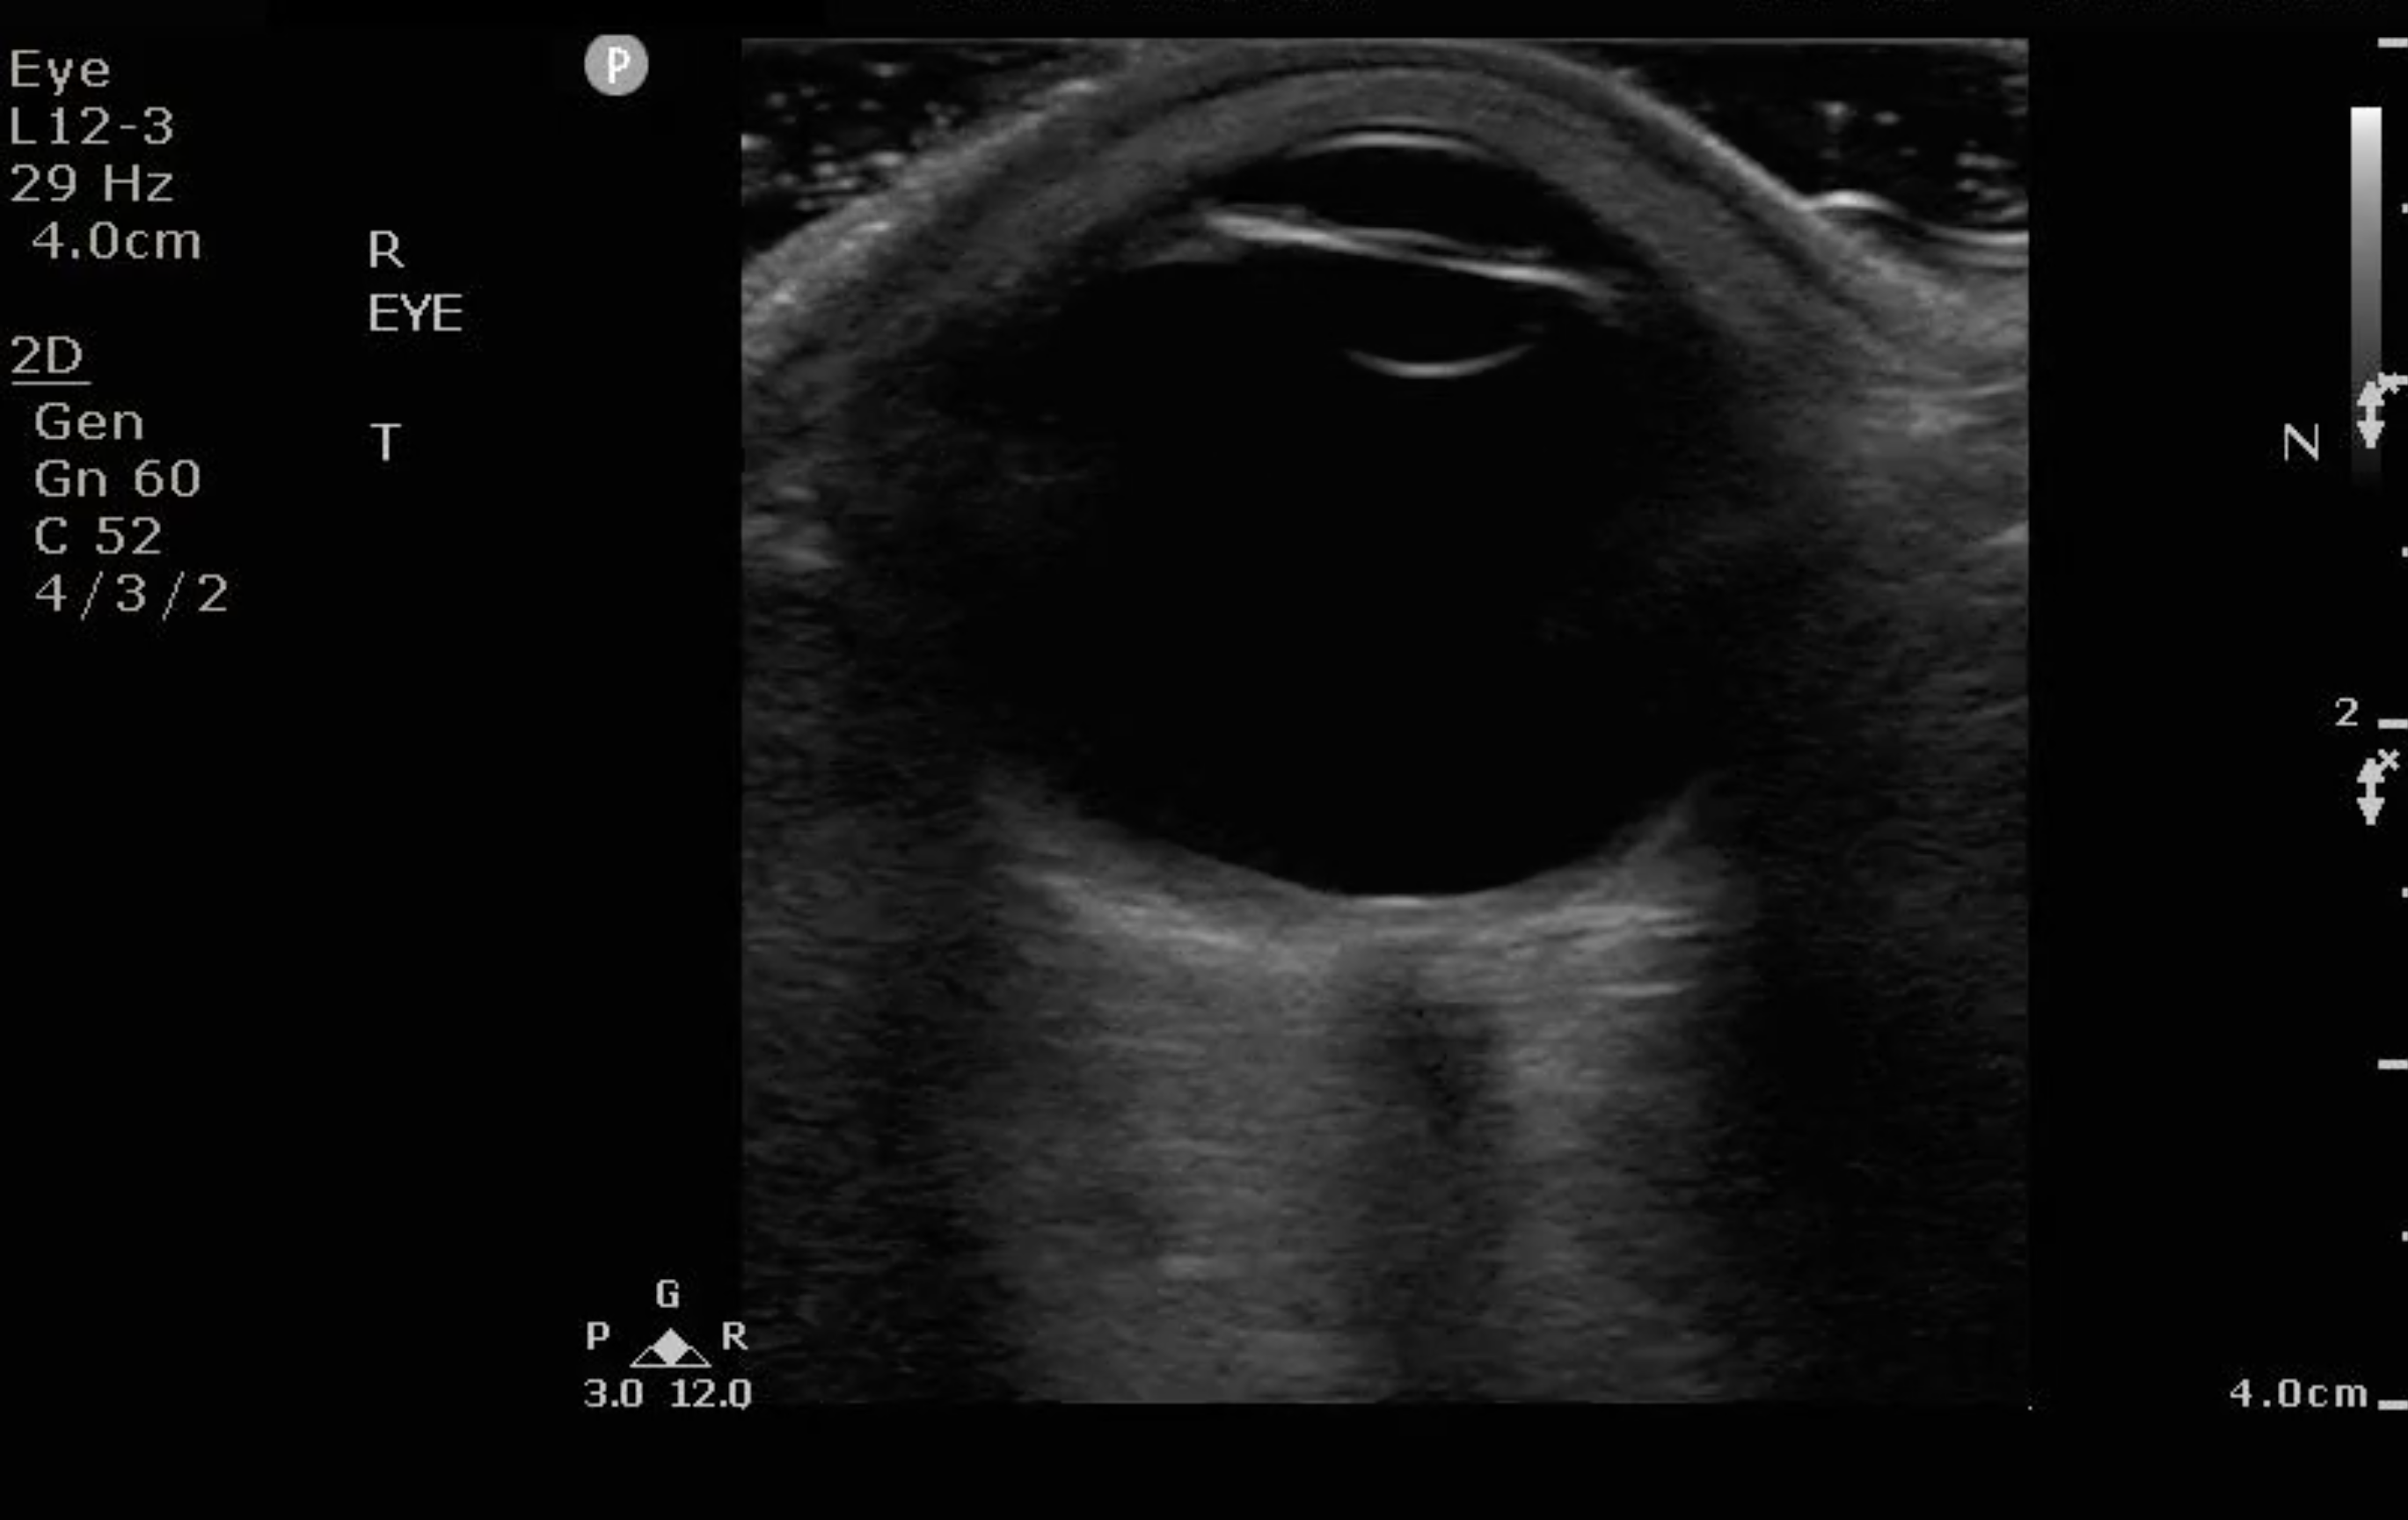

- Figure 3. Ultrasound image of a normal eye.

- Because the ocular chamber is fluid-filled, under ultrasound, it will appear as a round, anechoic structure.

- The most anterior structure seen, after the layer of ultrasound gel, is the eyelid.

- Just deep to the eyelid is the cornea and the anterior chamber. If too much pressure is applied during the ocular ultrasound examination, the anterior chamber may become compressed. It is important to avoid applying direct pressure to the eyelid.

- If the patient attempts to look down during the exam, you may be able to visualize the iris and pupil.

- The lens appears as a hyperechoic, curved line, located deep to the iris. If the patient has undergone cataract surgery, you may see two thin, hyperechoic parallel lines instead of the concave hyperechoic line.

- Normal vitreous humor will appear anechoic.

- The vitreous, retina, and choroid are located along the inside of the globe. Normally, you cannot differentiate one from the other.

- The most far field identifiable structure is the optic nerve. The parallel hyperechoic lines are the optic nerve sheath, since the optic nerve is hypoechoic and nondistinctive.